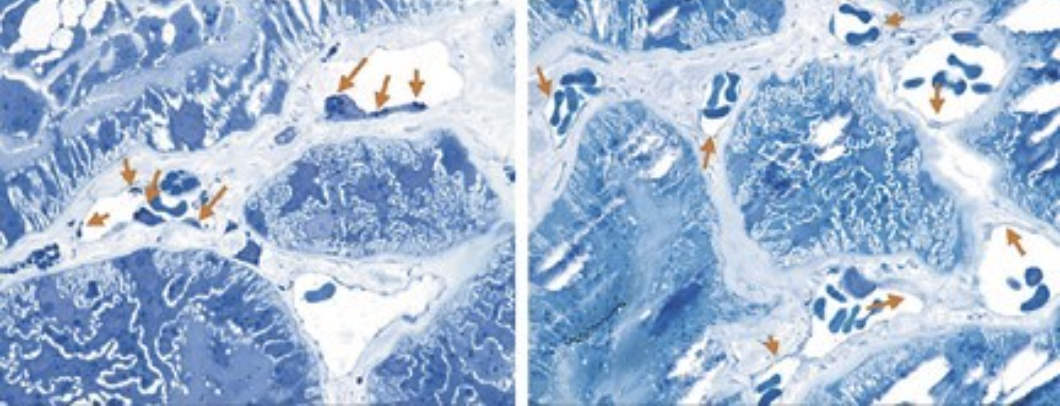

Acumulação de GL-3 nas células endoteliais capilares

A doença de Fabry é causada por uma variante patogénica no gene GLA que codifica a enzima lisossomal α-galactosidase A (também conhecida como α-GAL; α-Gal-A, e ceramida trihexosidase).1 A deficiência parcial ou total na atividade da α-GAL resulta na capacidade reduzida de catabolização de glicoesfingolípidos com resíduos terminais de α-galactosil. Estes glicoesfingolípidos, especialmente as globotriaosilceramidas (designadas por vezes como GL-3 ou Gb-3, ceramida trihexoside), acumulam-se nos lisossomas de vários tipos de células, incluindo as células endoteliais capilares, renais, cardíacas e nervosas, tendo como consequência o dano multissistémico progressivo.